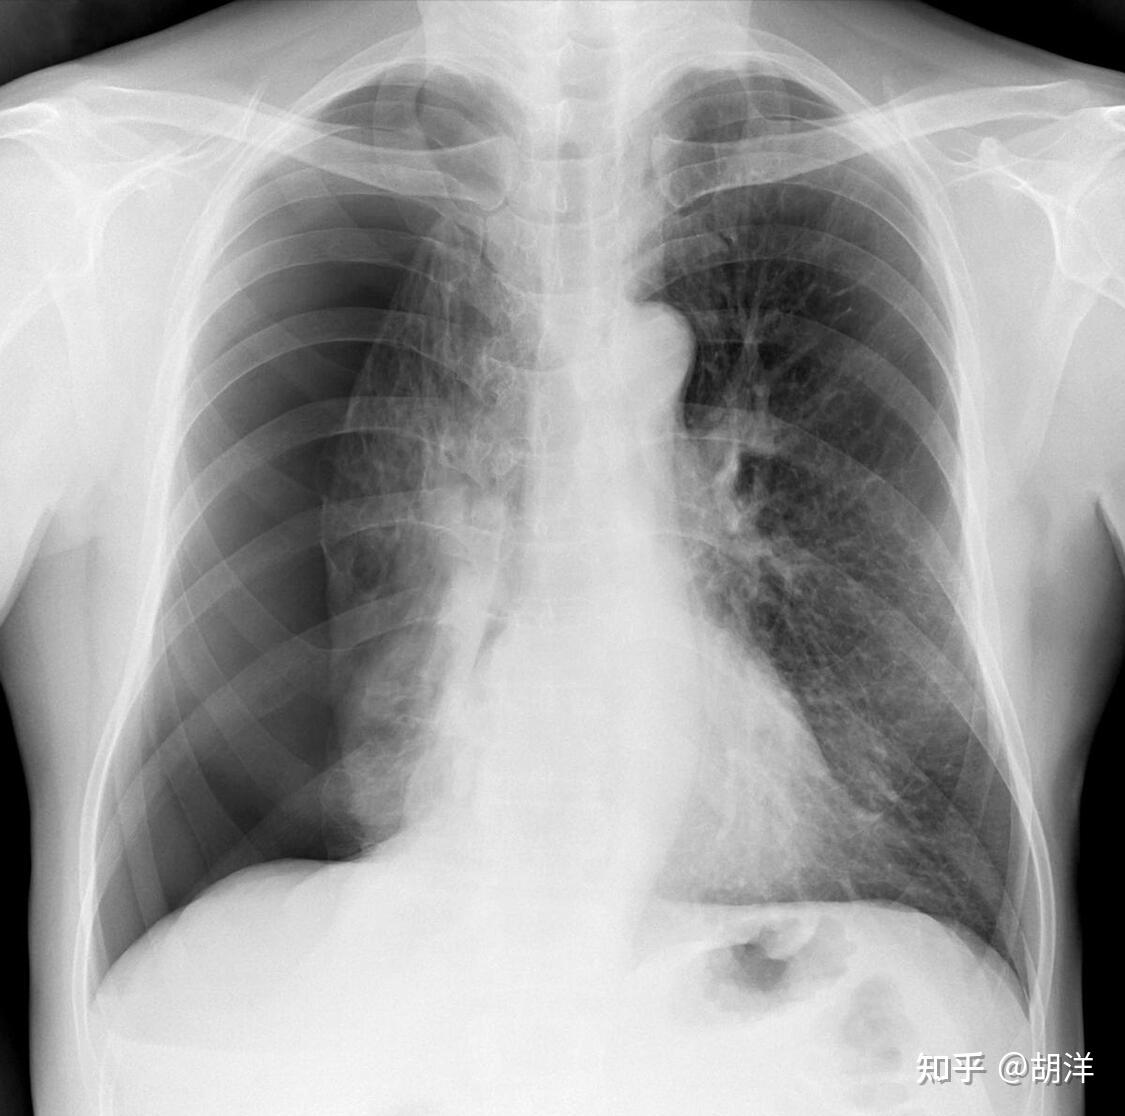

Medical Term Collapsed Lung. This air pushes on the outside of your lung. If it is a total collapse, it is called pneumothorax. A collapsed lung occurs when air escapes from the lung. A pneumothorax occurs when air leaks into the space between your. It can cause pain and extreme worry and certain cases can be. Pneumothorax is the medical term for a collapsed lung. Pneumothorax, also called a collapsed lung, is when air gets between one of your lungs and the wall of your chest. Here, find out why it happens and what to do if it does. Pneumothorax occurs when air gets in between the lung and the chest wall, causing the lung to collapse. A collapsed lung occurs when air leaks into the space between your lung and chest wall. A collapsed lung happens when air enters the pleural space, the area between the lung and the chest wall. The air then fills the space outside of the lung between the lung and chest. It can make the chest feel tight and breathing difficult.